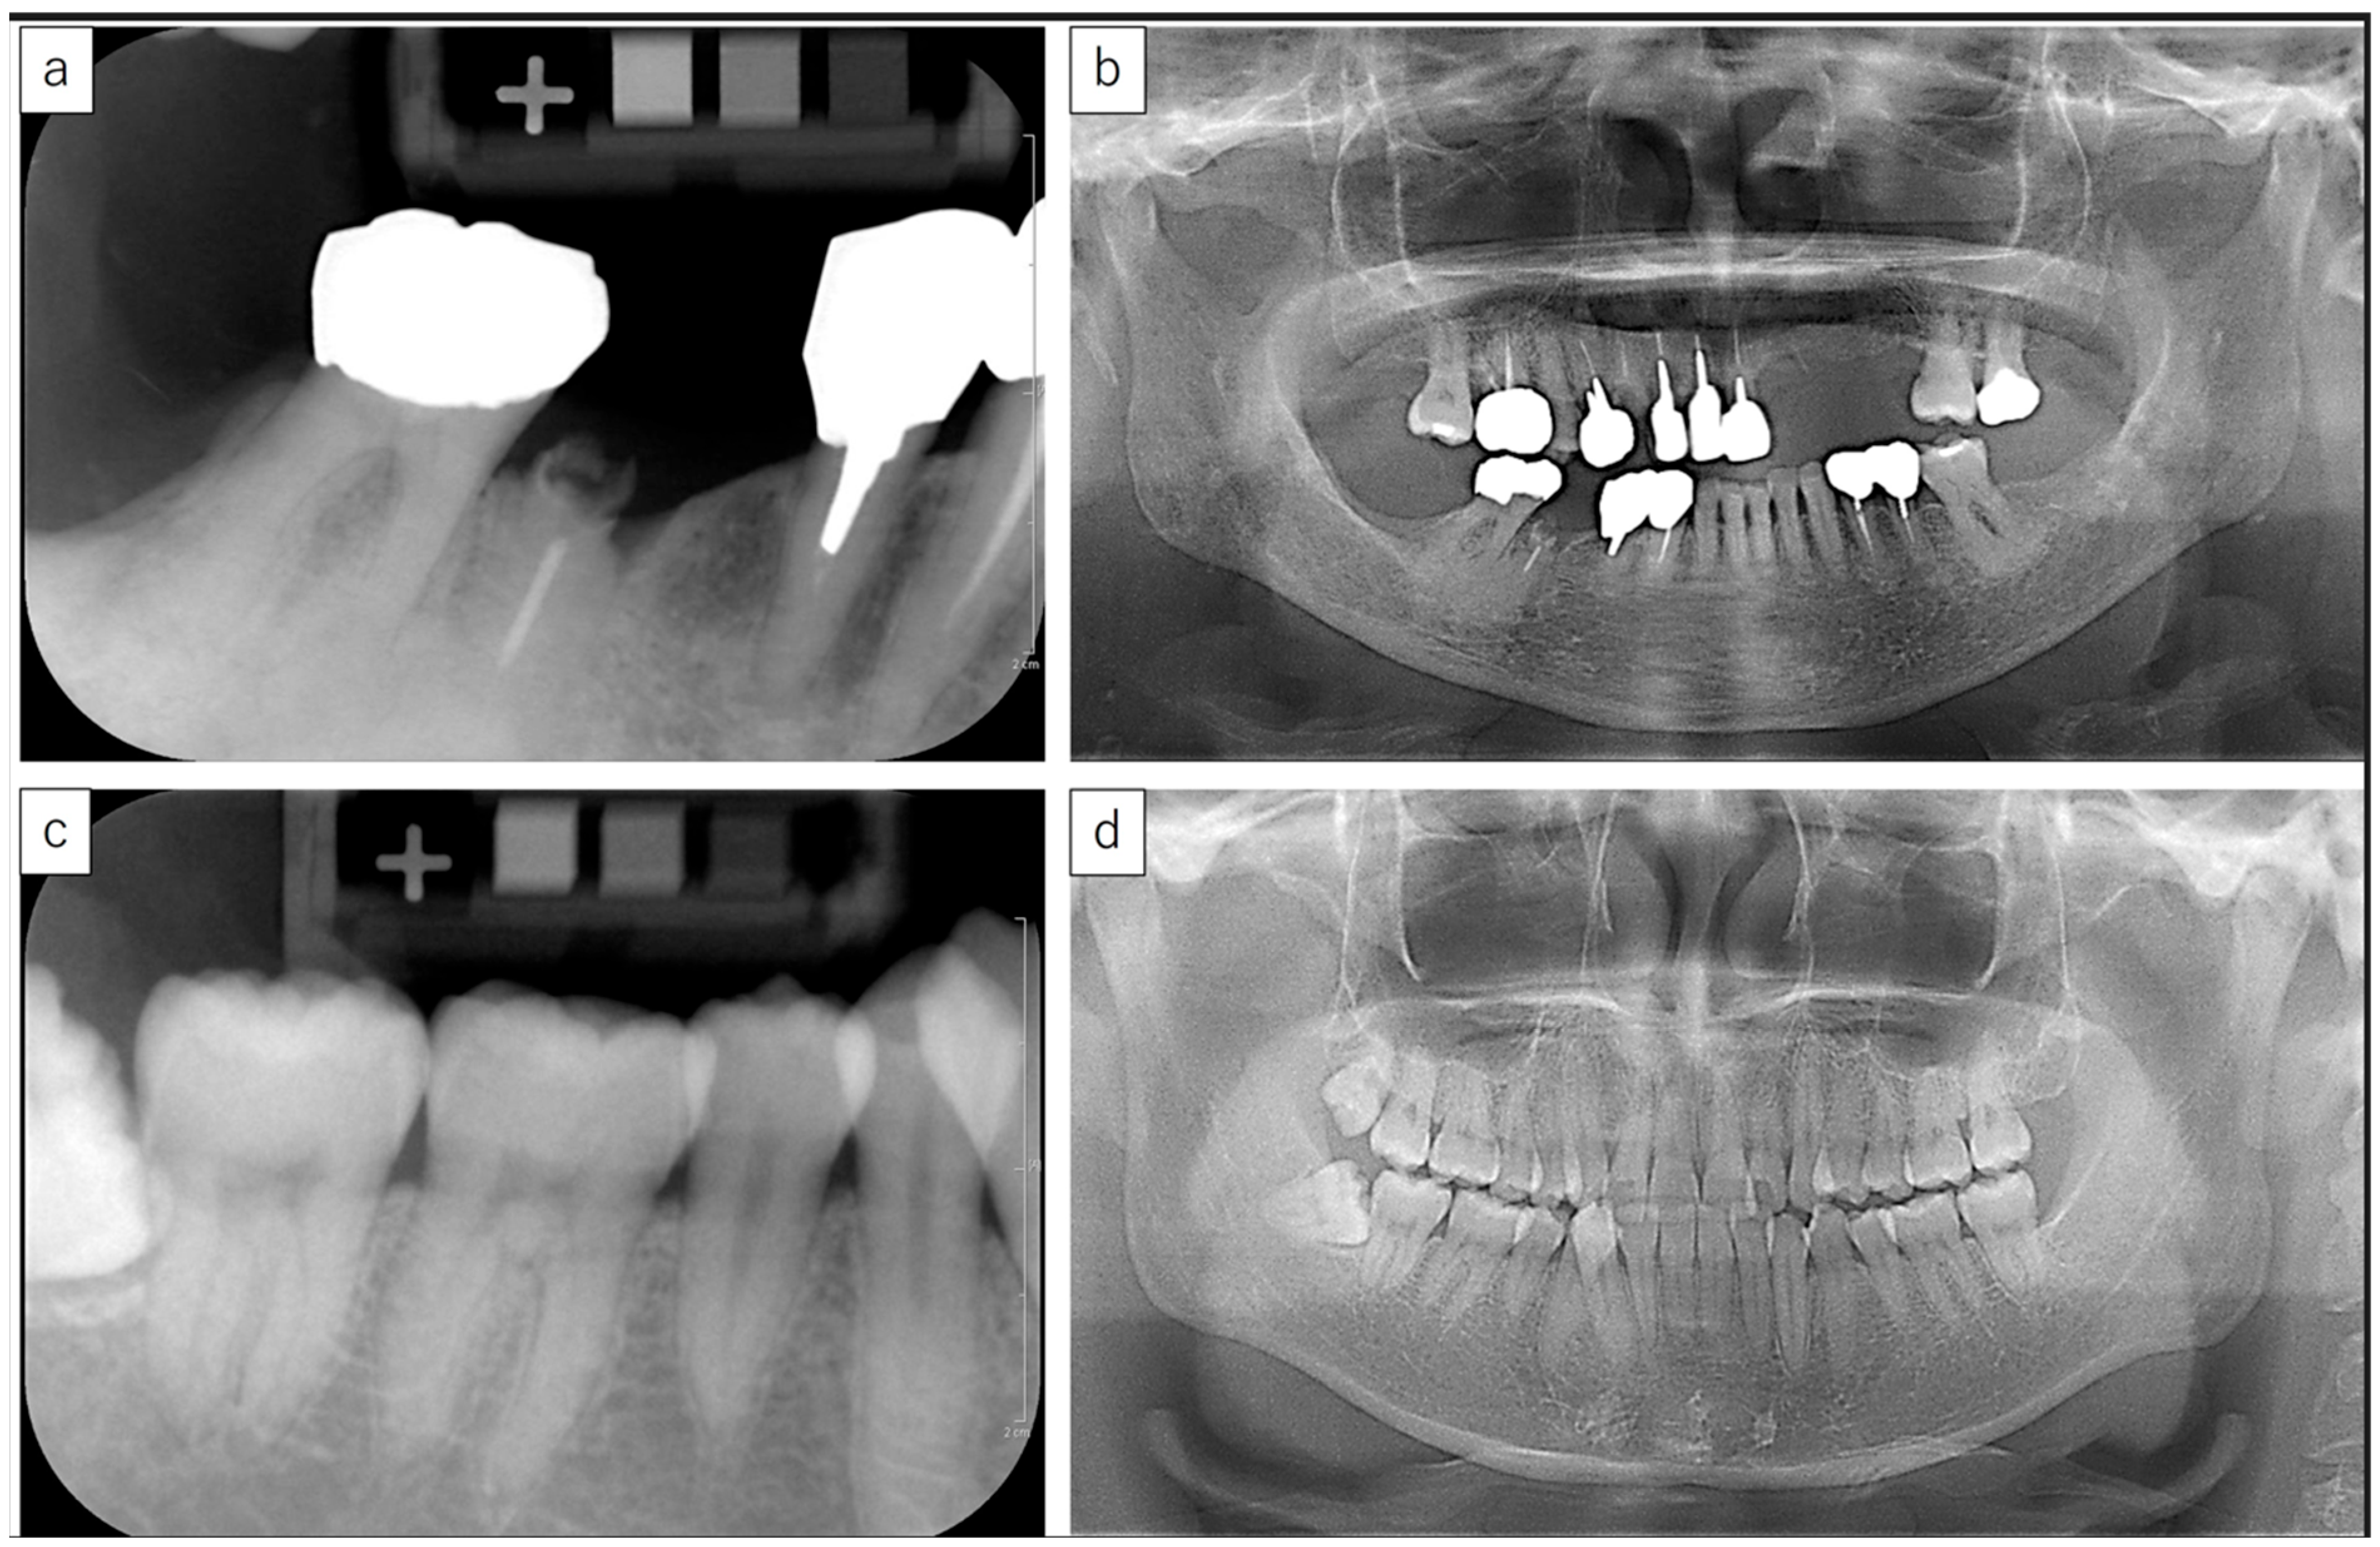

2.2. Intraoral Radiography and Bone Mineral Density Measurement

2.3. Panoramic Mandibular Cortical Index Evaluation